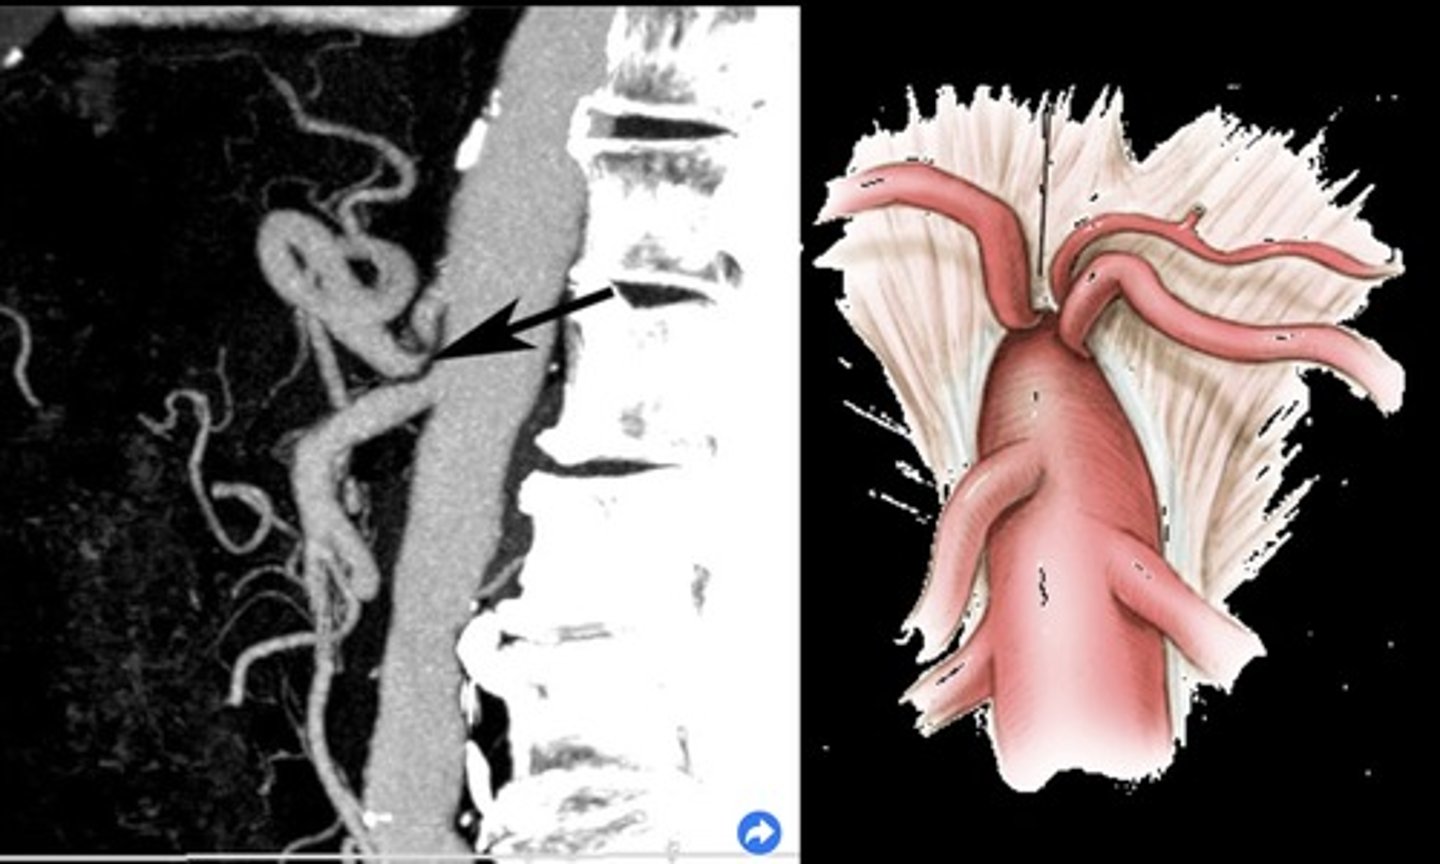

Dissection

Separation of channels - flap line

To and fro flow